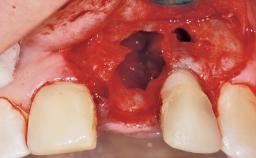

A 42-year-old female patient was referred to our clinic at the School of Dentistry of the University of São Paulo in November 2004, presenting a deficient restoration in the upper left central incisor. The clinical examination revealed no gingival retraction or any signs of gingival inflammation and, therefore, previous periodontal treatment was not considered. The patient presented a high lip line at full smile and a thin tissue biotype. This combination characterized a high-risk situation from an anatomic point of view, which required careful preoperative planning and cautious surgical execution.

Soft Tissue Anatomy Intact Defective

Bone Volume Horizontally and vertically sufficient Horizontally deficient Deficient vertically or deficient vertically AND horizontally

Socket Integrity Sufficient, with intact bone walls

Bone Volume Sufficient, with intact walls